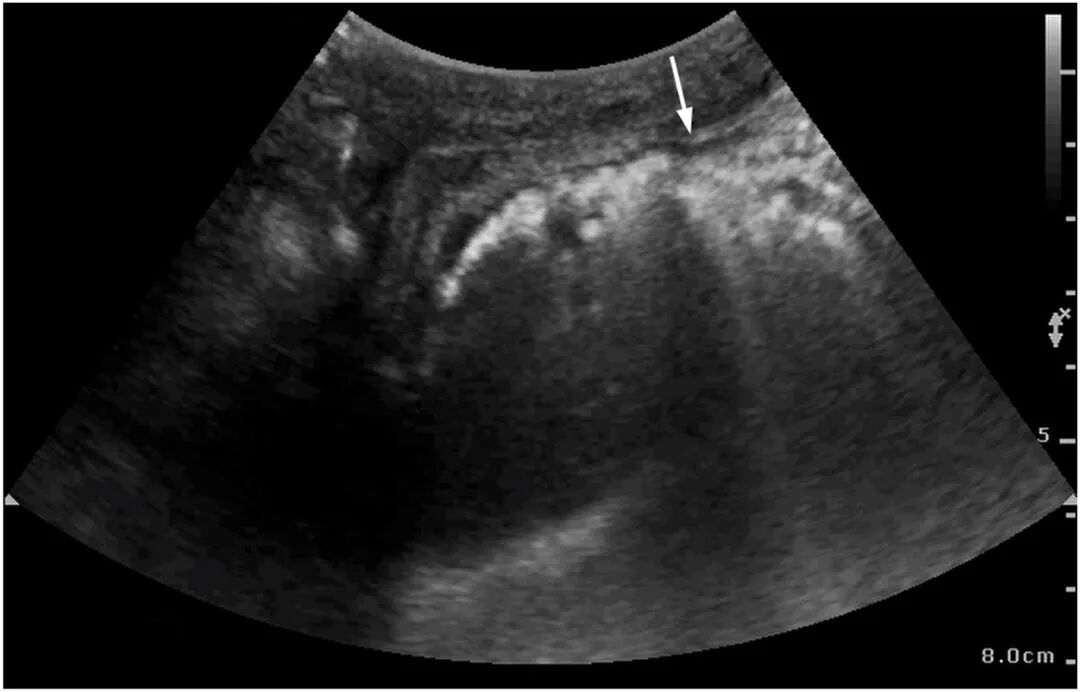

ICU第6日,患者因肠内营养不耐受出现轻微腹胀,C反应蛋白升高(199.69 mg/L),提示感染加重。鉴于病情变化,行床边即时超声检查,显示胃壁内出现“彗星尾”伪影(见图2、图3)。随后行腹部CT证实胃壁内气体积聚(图4)。

图3 床旁超声左肋间切面显示胃壁"彗星尾"伪影(箭头)